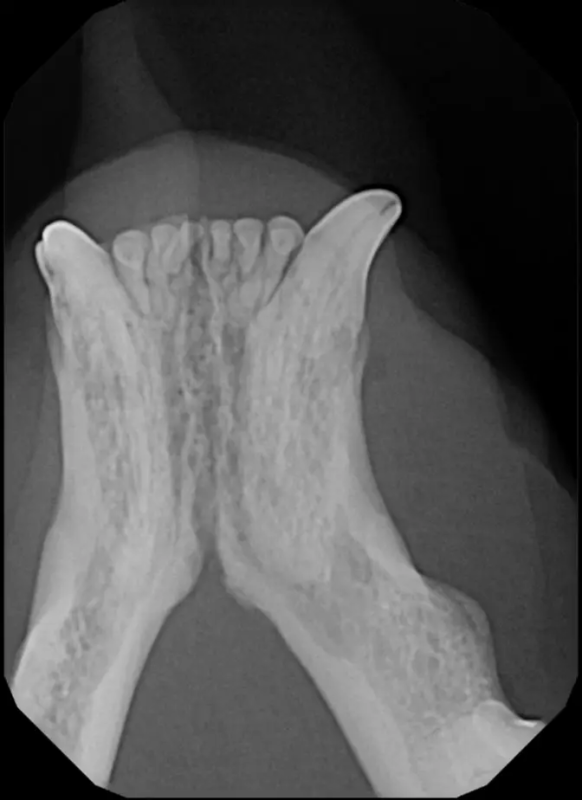

Root Canal Therapy

Root canal therapy is an excellent option for saving important teeth that have been fractured or are determined to be non-vital. The procedure is performed exactly as it would be for a human, except your pet will be dreaming peacefully under anesthesia. In many cases, root canal therapy is much easier on your pet than extraction, and preserves the structure of the tooth. It is important to have the root canal x-rayed periodically to monitor for any problems.

Vital Pulp Therapy

Young dogs less than 1 year of age that have very recently (less than 48 hours) fractured a tooth may be a candidate for vital pulp therapy. This procedure keeps the tooth alive and is very minimally invasive. For best results, this procedure should be performed within 48 hours of the tooth fracture. If your pet is not a candidate for this procedure, root canal therapy can still be performed to preserve the structure and function of the tooth. Vital pulp therapy can also be used to treat malocclusions.